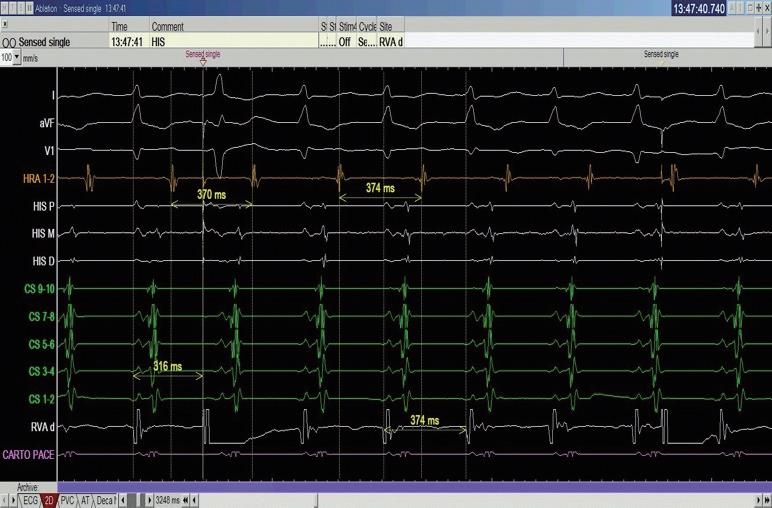

中華民國心律醫學會‧ Taiwan Heart Rhythm Soclety ‧中華民國 111 年 9 月出刊 我們在此報告一個來進行 PSVT 電燒的 55 歲 女性,沒有其他慢性病症,甲狀腺檢查正常,因為 PSVT 前往急診,發作時十二導程心電圖如下 ( 圖一 ) , 看起來是 short-RP 的 tachycardia 並且有 electrical alternans 的現象,第 12 個波組看起來比較不一樣,推測有可能 此時 tachycardia 有短暫的 termination 又被第 13 個波 組的 VPC 重新啟動一輪的 SVT 。 進入 EP lab ,在一開始進行 Ventricular extra stimulus test (VEST) 檢查時,心房訊號的傳導 是中軸傳導 (Concentric atrial activation pattern),而 且我們觀察不到明顯遞減傳導的現象 (Decremental conduction),一般而言正常經過房室結的傳導無論 順向或逆向多半會有 Decremental conduction 的情 況,這讓人懷疑隱藏在著一條在中軸的副傳導路徑 (Accessory pathway)( 圖二 ) 病人的心律不整很容易在右心房用 rapid pacing 誘 發,誘發時會看到心房心室傳導逐漸出現 Wenckebach 的現象,接下來就產生一個 Short-RP 的 tachycardia, 在 tachycardia 時的 atrial activation sequence 在 CS 導 程的表現看起來與我們先前在做 RV pacing 時是一致 的 ( 圖三 ) ( 圖二 ) ( 圖一 ) ( 圖三 ) 7NO.047

HIS refractory VPC 做確認時(圖五),結果又有點出乎 意外,當

中華民國心律醫學會‧ Taiwan Heart Rhythm Soclety ‧中華民國 111 年 9 月出刊 ( 圖四 ) ( 圖六 ) ( 圖五 ) ( 圖八 ) 我們接著進行 Para-hisian pacing 來證實我們的想 法,我們將原本放在 HRA 的電極放到在 Para-hisian 的 V site,邊做 pacing 邊調降 pacing voltage,一路將 voltage 降到 0.3mV 都可以 capture myocardial 並傳回 atrium 去,其中的 V-A interval 都保持一致,證實這個 accessory pathway 的存在(圖六)。 由於看起來是不管在 RV pacing 或心律不整跳起 來時 Atrial activation 都以 CS 9-10 最早,儘管 CS lead 在 fluoroscopy 的 LAO view 下放得比較深,我們先 在 Tricuspid ring 的 septal site 靠近 CS9-10 的地方進行 電燒。( 圖七 ) 我們在右側電燒時,不管是電燒或者 mechanical bump 的方式,都可以將正在跳的心律不整 終止。這時候心律不整下的 V-A 訊號看起來也比之前 寬,然而類似的心律不整依舊會被誘發。 我們於是考慮這條 accessory pathway 其實比較 broad band,並且牽扯到 LV 的 septum,最終我們成 功在 Mitral subvalvular 的 septal site 將這條 accessory pathway 燒掉,並且達到 complete VA block(圖八), 最終電燒位置即在先前右側電燒點的對面(圖九, 圖中 CS catheter 有外拉,電燒導管位置近似於圖七 CS 9-10)。 這時候為了區分 AVNRT 與使用 septal kent 作 為傳導的 orthodromic AVRT,或者有一個很長 PR interval 的 AT( 儘管在前面的誘發過程較為不像 ),我 們使用 RV 的導管做 overdrive pacing 來 entrain 這個 tachycardia。 在成功 RV entrainment 停止後,我們觀察 tachycardia 傳導回來的方式是 V-A-V response ,這 個反應排除了心房頻脈。接著我們計算 PPI-TCL 以 及 Stimulus-atrial interval minus ventriculoatrial interval (SA-VA),可以看到 PPI-TCL 數值為 114ms, 而 SA-VA 為 68ms。(圖四)PPI-TCL 剛好在一個邊 界值,是嗎?這裡有個小陷阱,我們應該要對 delta A-H 做校正,在本圖中因為 His 的訊號不明顯,所以我們 使用 delta A-V 做校正(假設 HV 為定值不太會變), 可以看到 PPI 的 A-V 因為 decremental properties 的 關係較長(280ms),而平常 tachycardia 在跳的時候 A-V interval 較短(194ms),校正後的 corrected PPITCL 其實是 114-(280-194)= 28ms。 從這樣的檢查代表應該是 septal accessory pathway 造成的 orthodromic AVRT,然而當我們進一步做

RV pacing 在 surface ECG 出現 fusion beat, 足以證實在 HIS refractory phase 時,並沒有 advanced 下一個 A,然而這樣是代表沒有 accessory pathway 存 在嗎?其實並不,因為單一 HIS refractory beat 不見 得真的能比從 His-Purkinjean system 傳下了的訊號更 早到達 accessory pathway,HIS refractory VPC 假設 有 advanced next A or terminate tachycardia 可以代表 有 accessory pathway 的存在,反過來並不能拿來證實 accessory pathway 不存在。 8 NO.047